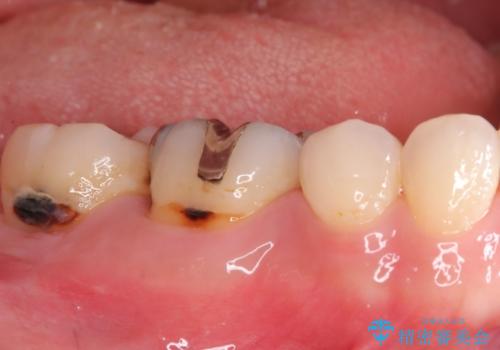

- 右下6番と7番の奥歯に、歯の根元部分の虫歯(根面カリエス)を認め来院されました。通常の虫歯よりも進行しやすい根面カリエスは、再発リスクを抑えた治療が重要です。患者様のご希望と口腔内の状態を考慮し、虫歯を徹底的に除去し、精密で耐久性の高いセラミッククラウンで修復する治療計画を立案しました。これにより、長期的な再発防止と咬み合わせの機能回復を目指します。

治療ではまず、感染した歯質をマイクロスコープで確認しながら慎重に除去。その後、セラミッククラウンを装着するための歯の形成を行いました。型取りから患者様の歯の形や色に合わせたオーダーメイドのセラミッククラウンを作製。セラミックは、プラークが付着しにくく、再治療のリスクを低減する特性があります。最終的に、精度の高いクラウンを装着し、咬み合わせを細かく調整しました。これにより、根面カリエスが再発しにくい環境を整え、快適に食事ができる奥歯を取り戻していただけました。